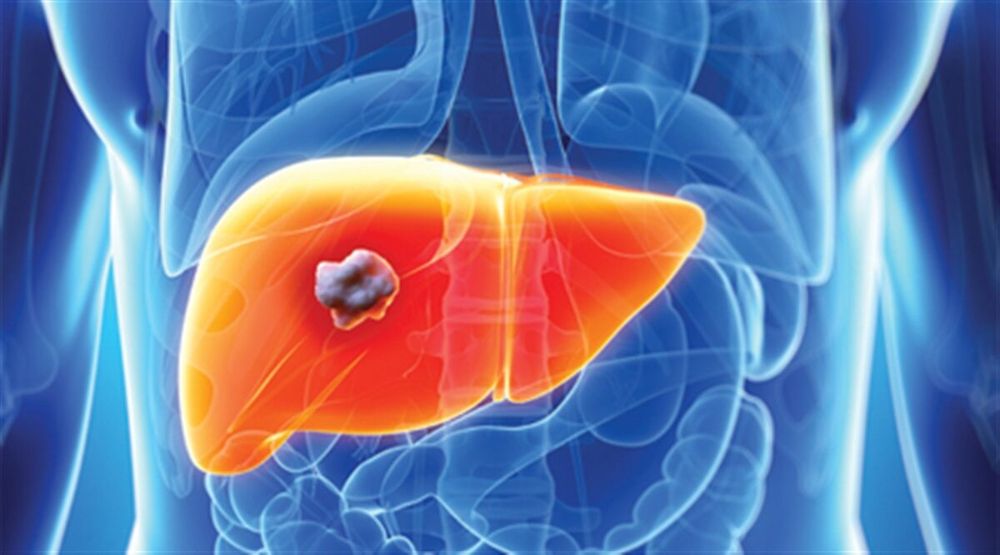

به گزارش «شیعه نیوز»، از سال ۱۹۹۰ به بعد، خطر ابتلا به سرطان کبد به طور نسبی دو برابر شده است. علائم این سرطان معمولا خود را نشان نمیدهند مگر این که به مراحل پیشرفته برسد. با این حال انجام آزمایشات مکرر شانس جلوگیری از این بیماری و میزان زنده ماندن در مبتلایان را افزایش میدهد.

در اینجا ۵ وضعیتی که شما را بیشتر در معرض خطر سرطان کبد قرار میدهد، معرفی شده است:

چاقی: شایعترین علت بالا رفتن آنزیمهای کبدی، کبد چرب است که البته علت آن هنوز نامشخص است. یکی از عوامل موثر بر این بیماری پرخوری و چاقی است؛ به خصوص در کسانی که چاقی شکمی دارند و اندازه کمربند شکمیشان بیشتر از حد طبیعی است. پزشکان هشدار میدهند که کبد چرب غیرالکلی میتواند به سرطان منجر شود.

به عقیده پزشکان گرایش به مصرف موادالکلی و شیوع چاقی در عصر حاضر به حدی افزایش یافته که اگر از هم اکنون اقدامات ضروری و پیشگیرانه صورت نگیرد میتواند موجب افزایش موارد جراحی در بیماران مبتلا به عارضه کبد چرب در آینده شود.

از دست دادن وزن: از دست دادن وزن و اشتها بدون داشتن رژیم غذایی خاص، با انواع بیماریهای مختلف از جمله تعدادی از سرطانها از جمله سرطان کبد ارتباط دارد. اگر در حال از دست دادن وزن بدون تلاش و رژیم هستید، با پزشکتان برای بررسی انواع بیماریها و جلوگیری زودرس از آنها مشورت کنید.

زرد شدن چشمها و پوست: این علائم زردی میتواند نشان دهنده سرطان کبد باشد ضمن این که شاید نشانهای از ابتلا به سرطان لوزالمعده نیز باشد.

ابتلا به هپاتیت سی: برخی ویژگیهای خاص ممکن است شما را در معرض خطر سرطان کبد قرار دهد. افراد با سابقه ویروس هپاتیت سی جزو افراد در معرض خطر هستند. با این حال درمان به موقع و زودرس هپاتیت سی از بروز سرطان کبد تا حد زیادی پیشگیری میکند.

ابتلا به هپاتیت ب: اگرچه این نوع هپاتیت با هپاتیت سی ارتباطی ندارد، اما میتواند منجر به سرطان شود. کودکانی که در بدو تولد واکسن این هپاتیت را دریافت نمیکنند، در معرض خطر سرطان کبد قرار میگیرند. مادر مبتلا به هپاتیت ب از طریق زایمان میتواند فرزند خود را مبتلا کند. افرادی که تزریق دارو با سرنگ مشترک انجام میدهند، شانس ابتلای بیشتری دارند.

پرسنل شاغل در مراکز بهداشتی و درمانی و کسانی که با مبتلایان به هپاتیت مزمن زندگی میکنند، مستعد این بیماری هستند. واکسن هپاتیت ب برای تمام نوزادان در بدو تولد و بالغین پر خطر توصیه میشود. همچنین تزریق واکسن هپاتیت بی مهمترین عامل پیشگیری از سرطان بوده که در همه کودکان در بدو تولد و بالغین با ریسک بالا توصیه میشود.